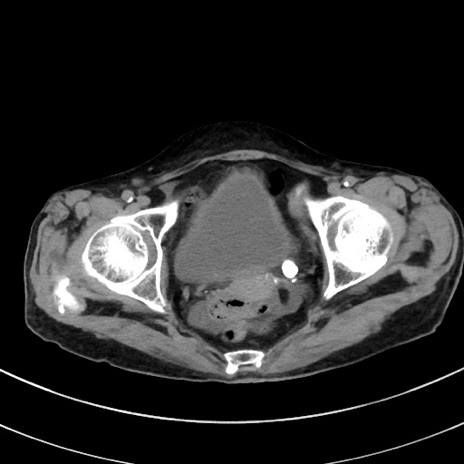

症例33(横断像)

【症例】70歳代 女性

【主訴】心窩部痛

【現病歴】延髄病変の精査・加療にて神経内科入院中。本日より心窩部痛あり。

【身体所見】右下腹部を中心に圧痛と反跳痛あり。